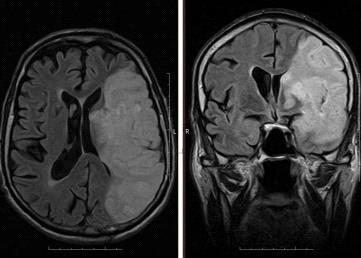

Примеры снимков представлены на рисунке 3.2 и 3.3.

Рис. 3.2 - ЛСМА (инсульт)